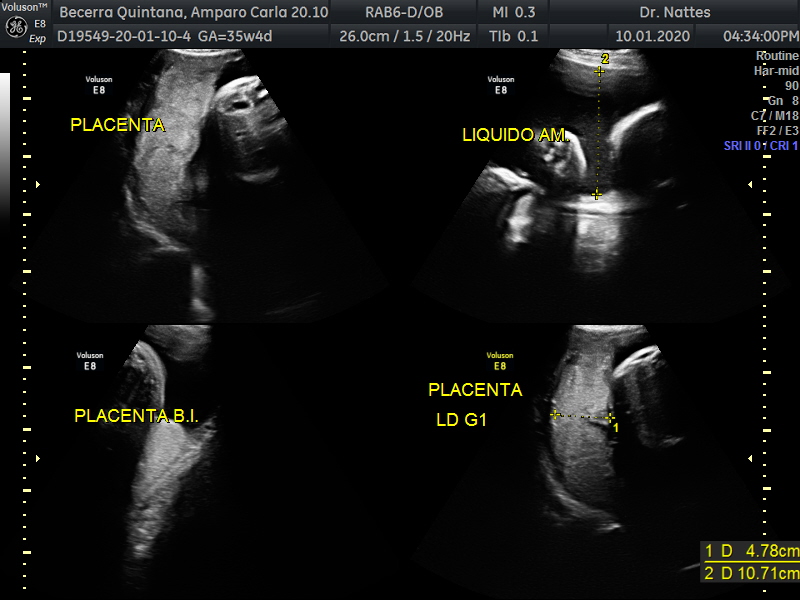

- El escenario Gravídico: Placenta, Liquido y Anexos.